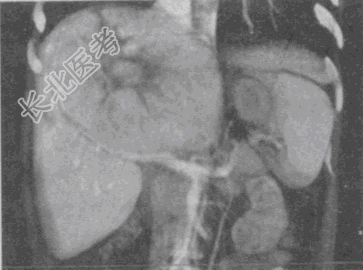

- 单项选择题男,54岁, 有乙肝病史,现腹胀, 右上腹痛,消化不良, 消瘦、乏力、贫血、黄疸,血清转氨酶升高, 白蛋白/球蛋白比值倒置,CT、MRI检查如图, 最可能的诊断是

C、原发性肝癌